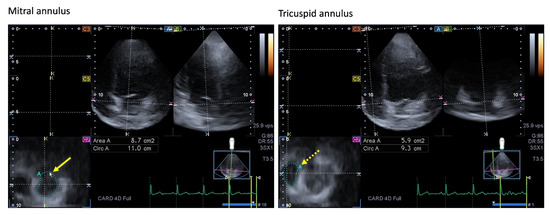

Long-Term Follow-Up of Professional Soccer Players: The Analyses of Left and Right Heart Morphology and Function by Conventional, Three-Dimensional, and Deformation Analyses

by Joscha Kandels, Michael Metze, Stephan Stöbe, Lisa Do, Maximilian Nicolas Möbius-Winkler, Marios Antoniadis, Andreas Hagendorff and Robert Percy Marshall

Background: Transthoracic echocardiography (TTE) is the primary imaging modality to assess cardiac morphology and function. In athletes, distinguishing physiological adaptations from pathological changes is essential. This study aimed to evaluate long-term cardiac structural and functional changes in professional soccer players. Methods: This retrospective study included 20 healthy male professional soccer players (mean age 21.2 ± 3.4 years) from the German first division, examined annually from 2016 to 2024 (mean follow-up 5.6 ± 2.0 years). TTE parameters associated with the “athlete’s heart” were assessed, including left ventricular end-diastolic diameter (LVEDD), interventricular septal thickness (IVSD), relative wall thickness (RWT), indexed LV mass (LVMi), and left atrial volume index (LAVi), along with 3D-derived LV and RV volumes. Advanced deformation imaging included global longitudinal strain (GLS), right ventricular strain (RVS), and left/right atrial reservoir strain (LASr and RASr, respectively). Baseline and final follow-up values were compared. Results: No significant changes were observed over time in conventional or advanced echocardiographic parameters (e.g., LVEDD: 54.5 ± 3.1 mm vs. 54.6 ± 3.9 mm; p = 0.868; GLS: −18.7% ± 2.2% vs. −18.4% ± 1.9%; p = 0.670). Ventricular volumes and strain values also remained stable throughout follow-up. Conclusions: Over a mean follow-up of more than five years, professional soccer players showed stable cardiac morphology and function without evidence of pathological remodeling. These findings support the concept that long-term high-level training in mixed-discipline sports leads to balanced, physiological cardiac adaptation. Full article

(This article belongs to the Special Issue Diagnostic Challenges in Sports Cardiology—2nd Edition)

Show Figures

Figure 1